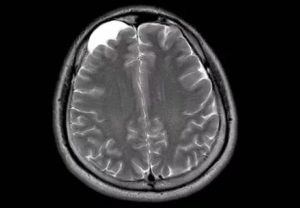

Картина арахноидальных изменений ликворокистозного характера в ходе исследований МР и КТ показывает наличие очагов с плотностью цереброспинальной жидкости, что подтверждает кистозную, неопухолевую природу образования.

Несмотря на то, что КТ позволяет точно определить размеры и расположение кисты, наиболее точную и полную информацию об образовании дает МРТ. Обычно для диагностики арахноидальной кисты проводится МРТ-сканирование с введением в кровоток пациента контраста.

Также МРТ-сканирование позволяет отличить кисту от кровоизлияний, гематом, гигром, абсцессов и других заболеваний со сходной симптоматикой. Кроме того, МРТ дает возможность выявить кисту даже в тех случаях, когда у пациента еще нет никаких проявлений, а сама киста имеет размеры всего в несколько миллиметров.